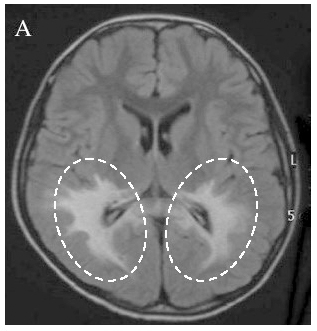

Figure 2. MRI image of a patient with X-linked adrenoleukodystrophy

In the brain of a patient with the cerebral form of X-linked adrenoleukodystrophy, areas of demyelination—where the protective covering of nerve fibers is damaged—can be seen (outlined by the dotted lines in the image). (Reproduced with permission from the Gifu University ALD & Peroxisomal Disease website)